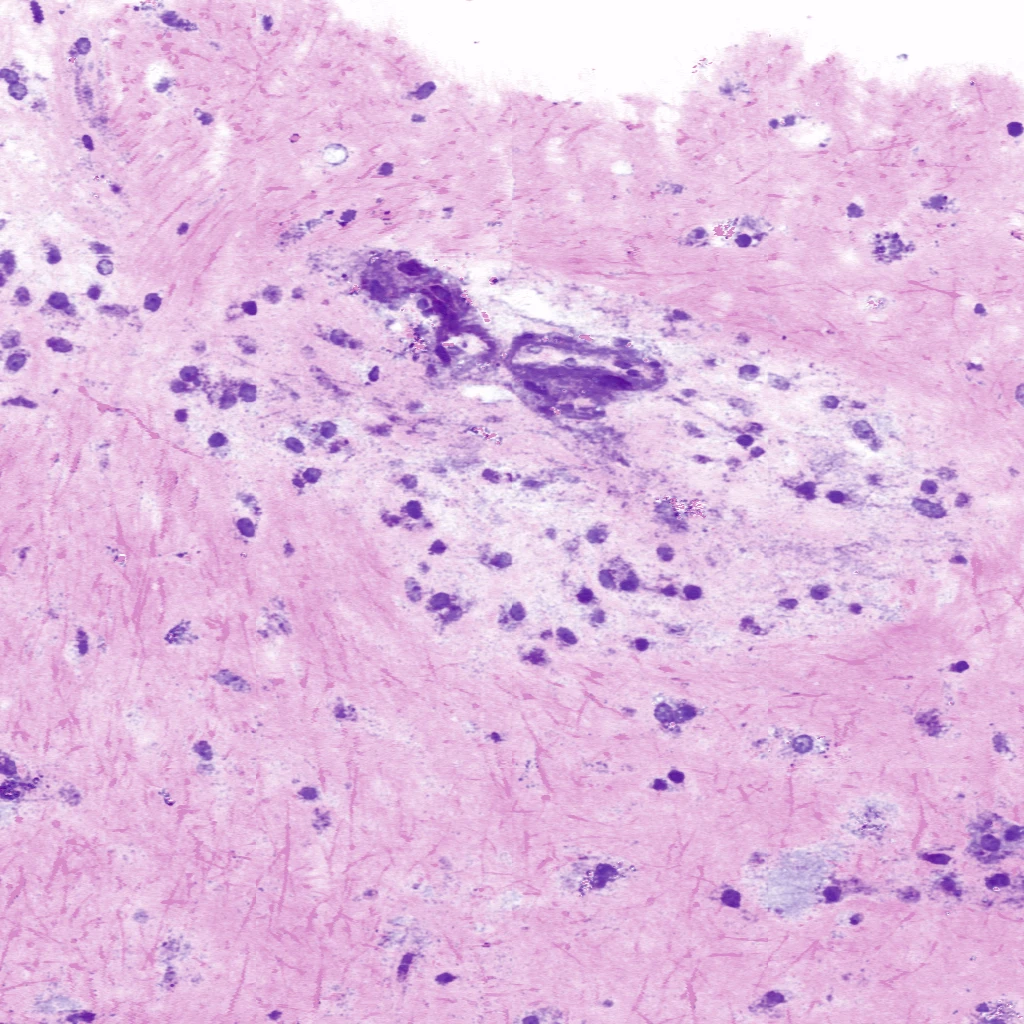

Virtual H&E image of a Glioblastoma tissue